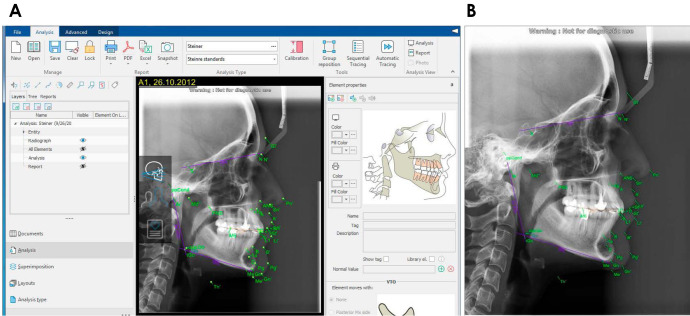

Purpose: The aim of this study was to compare the accuracy of AI-based AudaxCeph software, Dolphin software, and the manual technique for identifying orthodontic landmarks and tracing lateral cephalograms.

Materials and methods: In this cross-sectional study, 23 anatomical landmarks were identified on 60 randomly selected lateral cephalograms, and 5 dental indices, 4 skeletal indices, and 1 soft tissue index were measured. Each cephalogram was traced using 4 different methods: manually, with the Dolphin software, with the AudaxCeph software automatically, and with the AudaxCeph software in semi-automatic mode. The intra-class correlation coefficient (ICC) and Bland-Altman plots were used to evaluate the agreement between methods. Inter-observer and intra-observer agreements, calculated using the ICC, confirmed the accuracy, reliability, and reproducibility of the results.

Results: There was strong agreement among the AudexCeph (semi-automated or automated) AudaxCeph, Dolphin, and manual methods in measuring orthodontic indices, with ICC values consistently above 0.90. Bland-Altman plots confirmed satisfactory agreement between both versions of AudaxCeph (semi-automated and automated) with the manual method, with mean differences close to 0 and about 95% of data points within the limits of agreement. However, the semi-automated AudaxCeph showed greater agreement and precision than the automated version, as indicated by narrower limits of agreement. The ICC values for inter-observer and intra-observer agreements exceeded 0.98 and 0.99, respectively.

Conclusion: The semi-automated AudaxCeph software offers a robust and cost-effective solution for cephalometric analysis. Its high accuracy and affordability make it a compelling alternative to Dolphin software and the manual method.